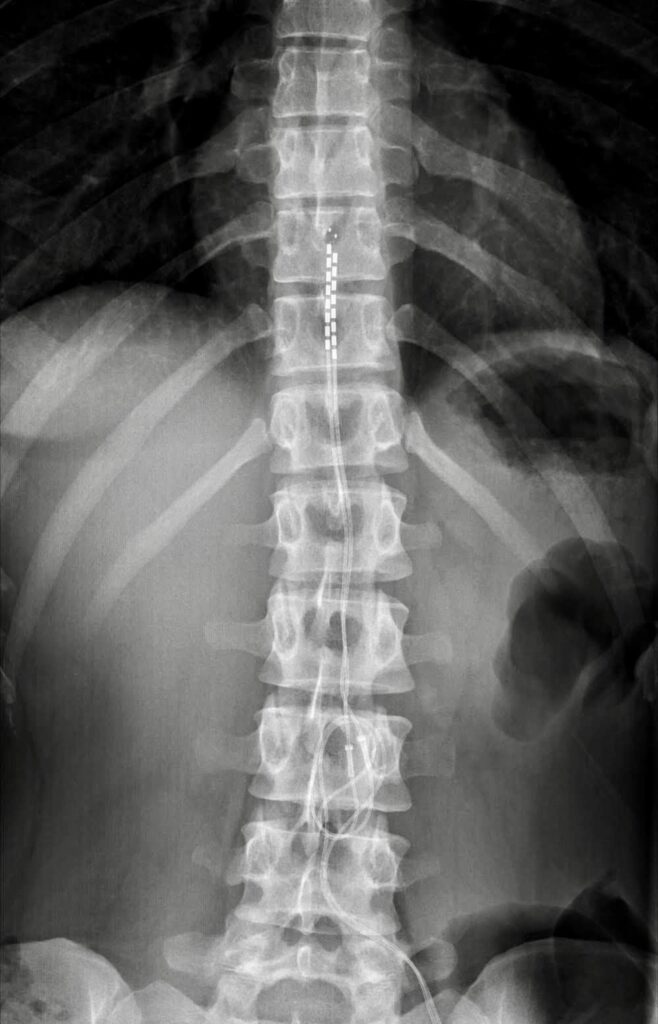

NEUROSTIMOLAZIONE MIDOLLARE

La Neurostimolazione Midollare o Spinal Cord Stimulation permette attraverso sistemi impiantabili percutanei come elettrodi e generatore di impulsi (pacemaker), di creare un campo elettromagnetico attorno al midollo spinale, in grado di interferire sulla conduzione del dolore cronico neuropatico.